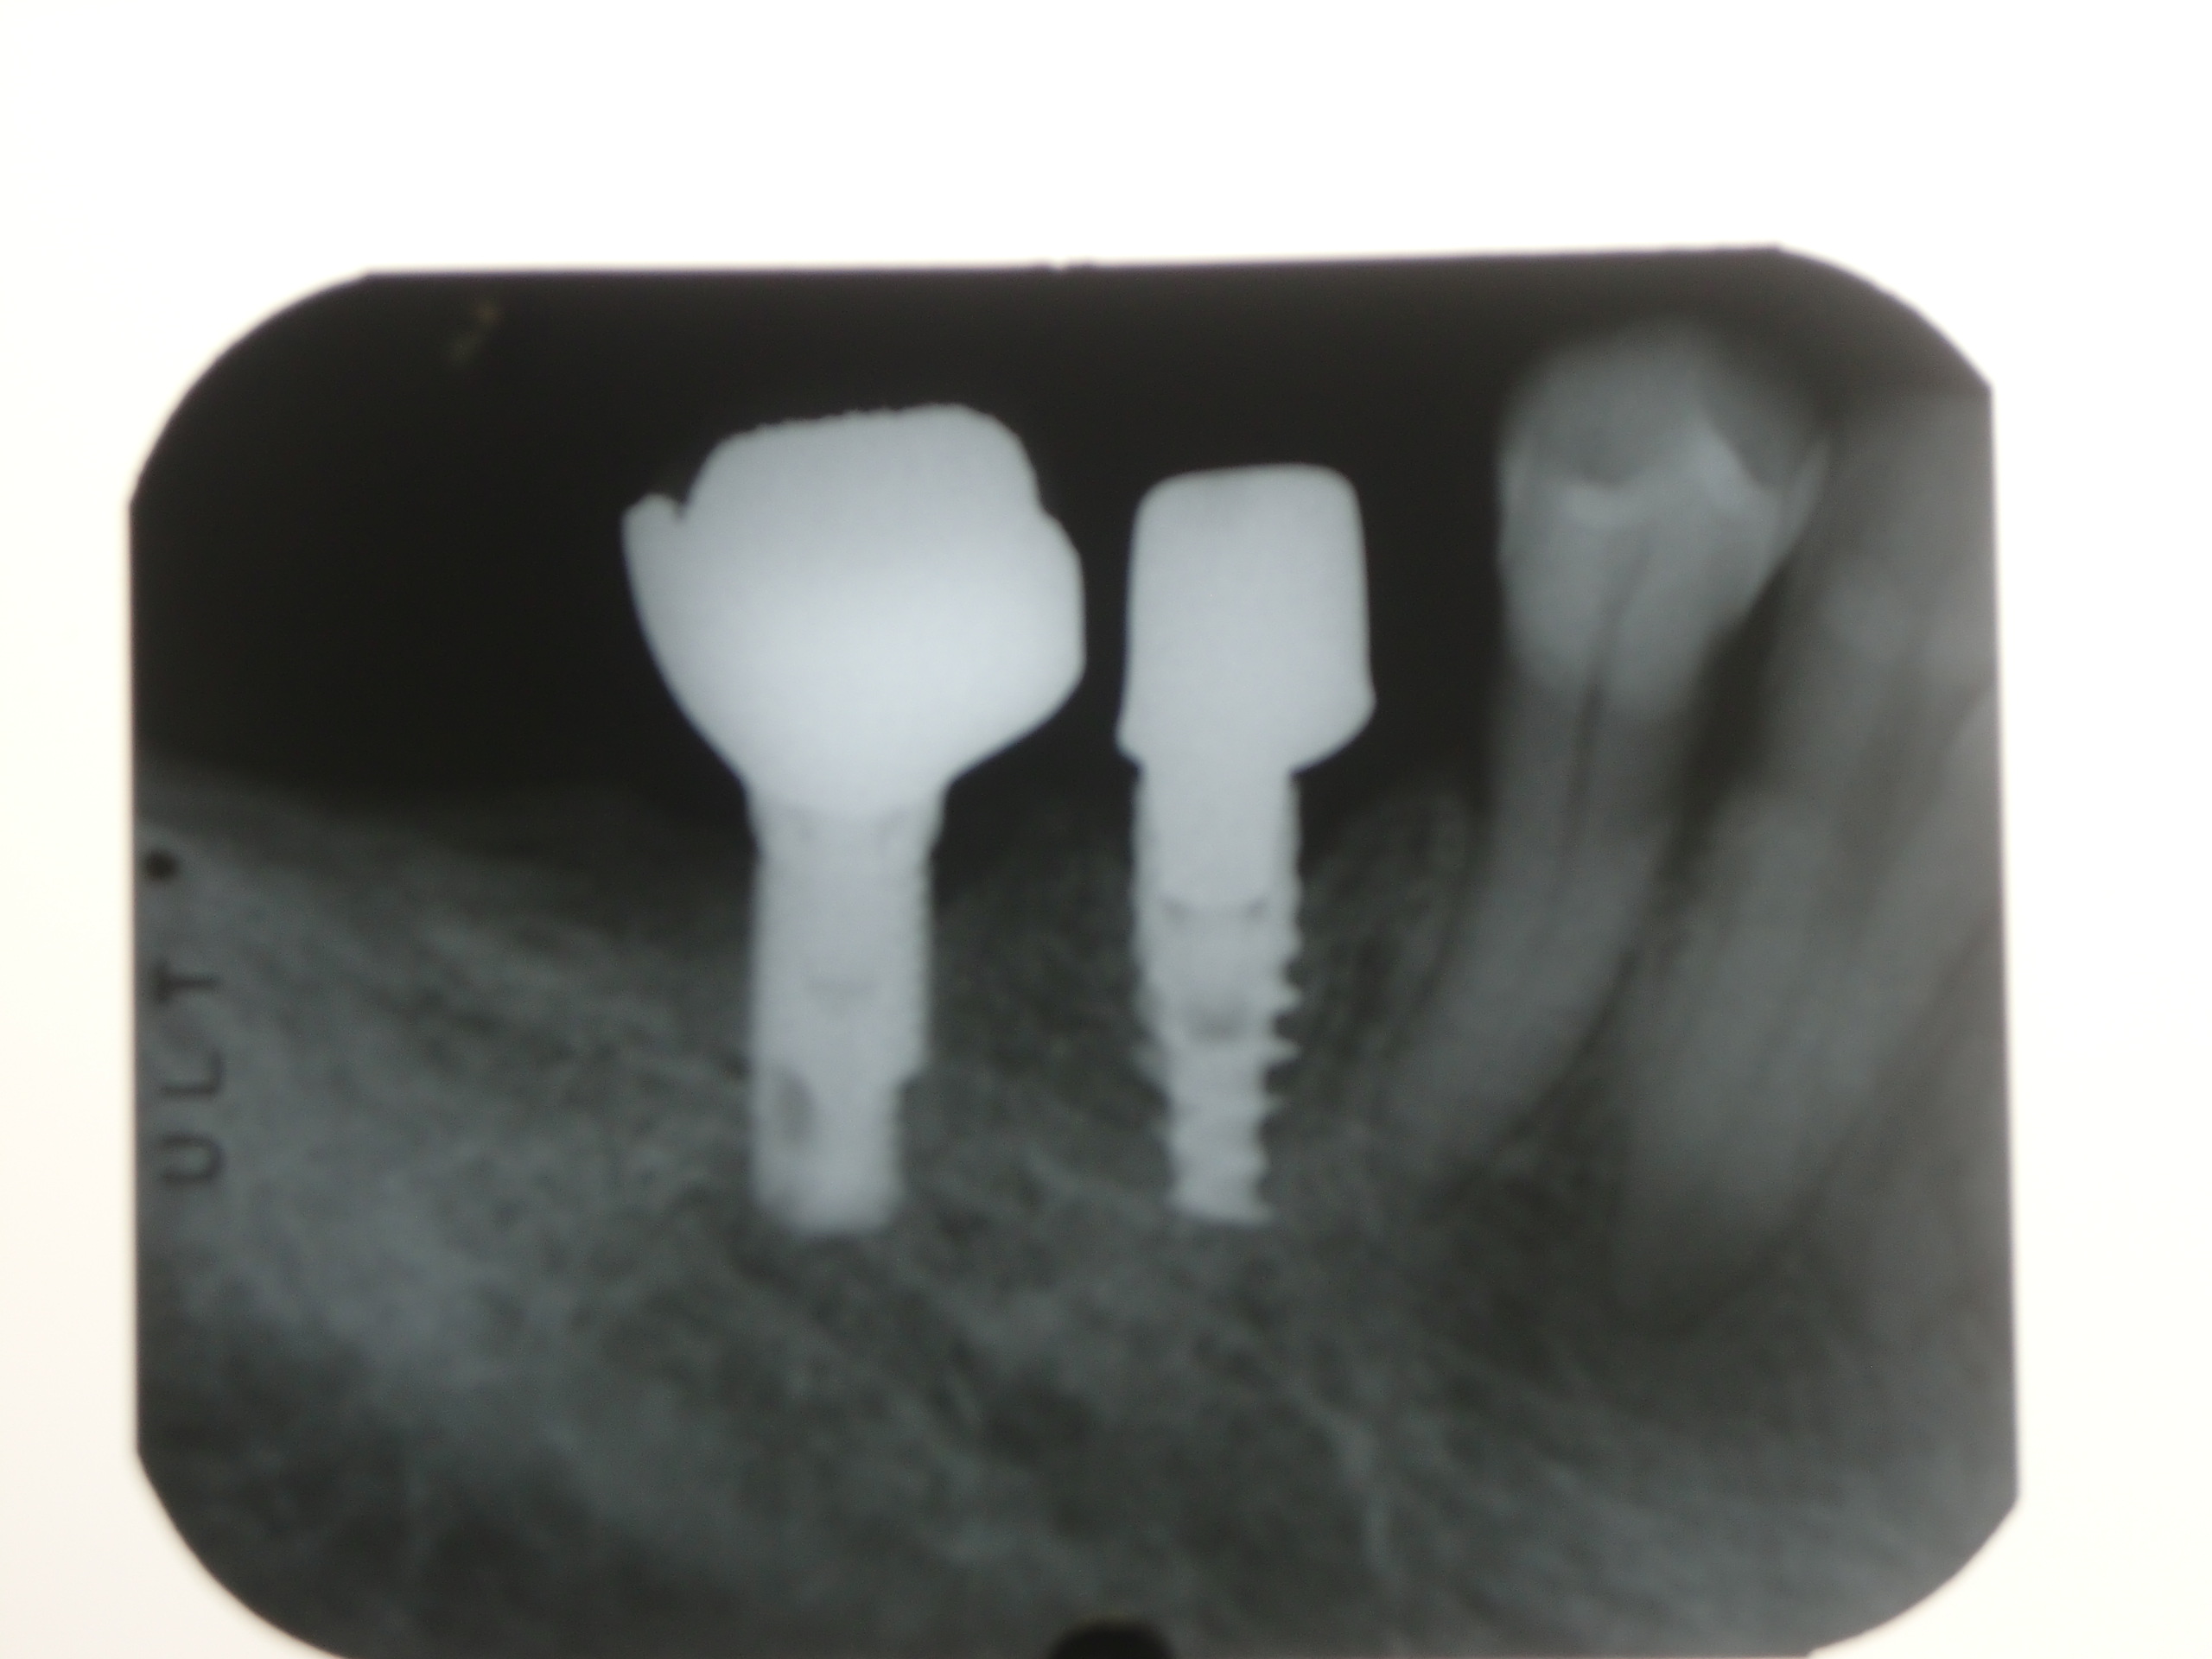

上2番目の歯をインプラント治療をしています(左から2本目) まだプロビジョナル(仮歯)です 最近プラスチックサージェリーという言葉を聞きませんか? 歯肉美容整形オペという意味です もともとプラスチックとは偽物とか仮のとかいう意味であまりよい意味では使いません。 われわれがおこなっているオース…